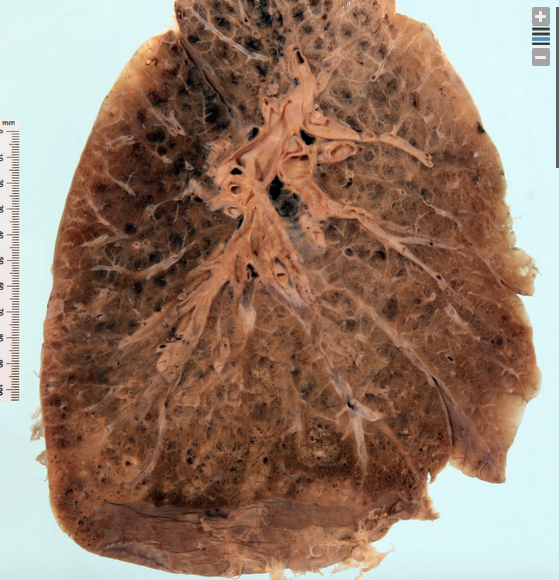

Emphysema, small areas of pneumonia in base